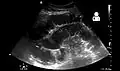

- Small bowel obstruction on ultrasound[19]

Small bowel obstruction on ultrasound[19]

Radiological signs of bowel obstruction include bowel distension (small bowel loops dilated >3 cm) and the presence of multiple (more than 2) air-fluid levels on supine and erect abdominal radiographs.[16] Ultrasounds may be as useful as CT scanning to make the diagnosis.[17]